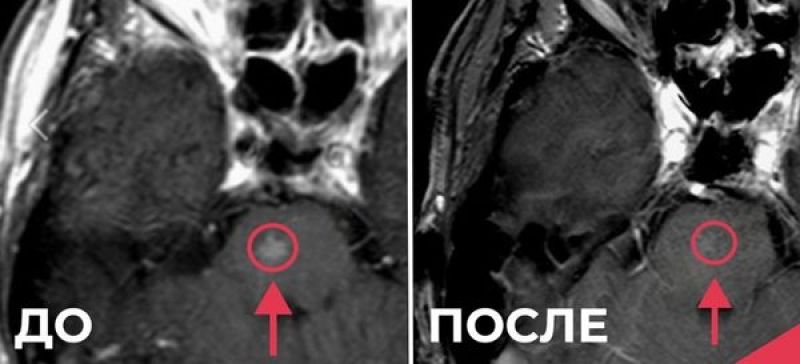

Спустя 4 месяца после окончания лечения при МРТ был выявлен метастаз в ствол головного мозга.  В июле прошлого года мужчине выполнена радиохирургия инновационным методом с применением некопланарных гипер-арок (HyperArc).

Спустя 13 месяцев после операции в стволе головного мозга пациент живет активной жизнью и продолжает лечение рака легкого, добавили в ведомстве.